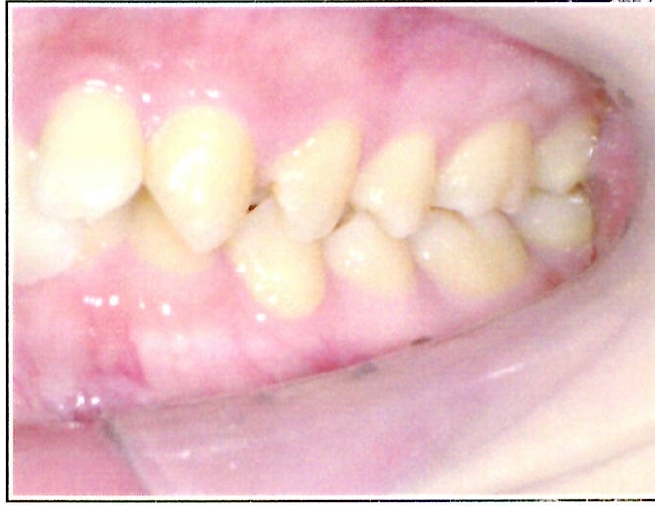

| 主訴・治療前の状態 | 下顎前歯部に叢生(ガタガタ)があり、歯ブラシが届きにくく清掃性に問題がありました。また、見た目も気にされていました。 |

| 治療内容 | 下顎前歯を1本のみ抜歯し、歯列を整えました。治療に際しては、ブラックトライアングル(歯と歯の間の歯茎部分に三角形の隙間ができること)が生じる可能性について事前に説明し、患者様にご了承いただいた上で治療を開始しました。 |

| 治療結果 | 予定通りの仕上がりとなり、事前説明の通りブラックトライアングルは生じましたが、患者様には十分ご理解いただいており、満足度の高い結果となりました。 |